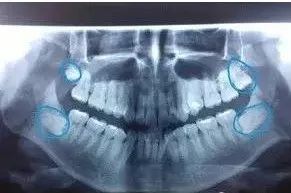

智齿在X线片上很清晰↓↓

*理论上人应该会有四颗智齿,但是一般不会全部长出来,很多人只会长出一颗或两颗,也有可能智齿是完全埋伏的,隐患和拔除难度都比较大。

完全埋伏在骨内的阻生智齿,如果与邻牙牙周不相通,又没有疼痛,可以暂时保留,因为这种埋伏牙可能终生无害而且拔除困难(需口腔医生拍X线片确认)。

对于这种没长出来的智齿,要定期拍片观察。拍了片子得评估,不管是竖着阻生,还是横着阻生,但凡有潜在的危害,最好及时拔除。